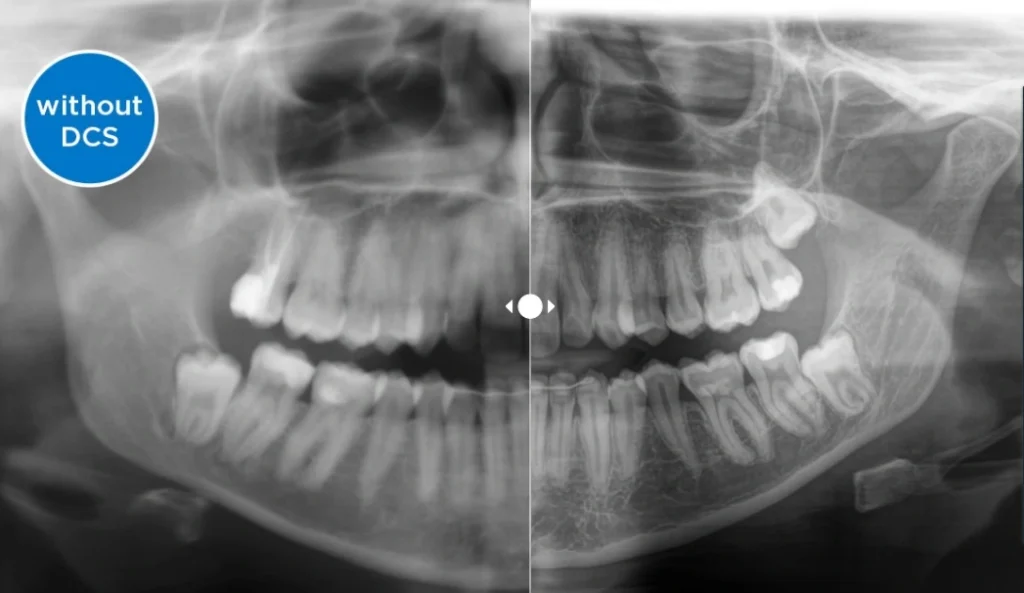

IMÁGENES RADIOGRÁFICAS MÁS NÍTIDAS QUE NUNCA !!! Nuevo Sensor de conversión directa (Direct Conversion Sensor, DCS):

El sensor de conversión directa (DCS) ha revolucionado el estándar de la radiología panorámica. Los rayos X se convierten directamente en señales eléctricas. Por lo tanto, no hay pérdida de señal debido a la conversión de la luz, como ocurre con los sistemas convencionales. El resultado: imágenes con un alto nivel de nitidez y contraste, incluso con una dosis de radiación extremadamente baja. Para obtener información para hacer un diagnóstico preciso, que respalde el tratamiento dirigido.

La siguiente imagen muestra una radiografía panorámica sin y con tecnología DCS. Con la flecha, arrastra el control por la imagen para ver la diferencia que supone el sensor de conversión directa en cuanto a la calidad de la imagen y las posibilidades de diagnóstico.